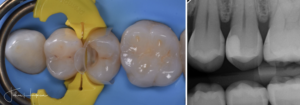

En typisk mun efter 30 år med komposit. Patienten lider av food impaction och är trött på att få göra om fyllningar varje år. Bild: Johan Hagman

Med Bioclear metoden – anatomiskt korrekt restauration utan kompositöverskott eller food impaction Bild: Johan Hagman